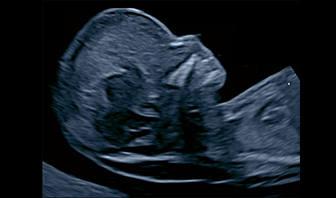

初期胎児ドック(11-13週)では正確なNT計測と全身チェックをして、ダウン症の確率が計算されます。この時期から脳や心臓・顔や手足などの異常がはっきりわかることもあります。

中期ドック(18-21週)では胎児の脳ドックを含めて全身に奇形や異常がないか30項目以上の検査をします。

後期ドック(29-30週)になると分娩に向けてしっかり脳やその他の器官が発達しているか見ていきます。

超音波による精密検査は、お腹の赤ちゃんの脳や各臓器、鼻の骨やNT(むくみ)などを部位ごとに確認し、異常を検知します。まずは超音波検査で異常の有無を確認したうえで、必要に応じて遺伝学的な検査実施をご提案しています。

初期ドックでは赤ちゃんにむくみ(NTと呼ばれています)がないか、鼻骨や顔面、耳の位置などの異常がないか、初期脳内の中脳水道や脳室、心臓の向き、心臓の4腔、胃の位置・へその緒の血管数・心臓内や心臓に入る前の血管の血流などのチェックを行います。染色体異常でもダウン症や18トリソミー、13トリソミー、ターナー症候群など染色体の種類により、特徴的な構造を初期から示します。その他の先天性異常の可能性もかなり細かく評価でき、初期に現れる脳異常がないかなどもチェックします。染色体異常については中期ドックよりも検出率が高いのが特長です。

中後期ドックでは、赤ちゃんの脳ドックや心臓の構造・手足の指や口唇や顎、白内障などのチェックまで30項目以上にわたるチェックをシステム的に行います。脳ドックでは、現在生まれてからしかほとんどわからないとされている「大脳皮質形成異常」などの早期スクリーニングも含まれています。

クリフムの胎児ドックでは、赤ちゃんの脳について「大きさが週数相当か」といった確認にとどまらず、脳がどのような過程で発達しているかという点まで観察しています。

一般的な妊婦健診ではお腹の上から超音波を当てて観察しますが、クリフムでは「経腟超音波(下から見る超音波)」を用いた胎児脳診断を行います。

赤ちゃんの頭の骨は超音波を通しませんが、おでこの上には「大泉門」と呼ばれる骨のないやわらかな部分があります。この大泉門を通して観察することで、脳の内部構造をより詳しく確認することが可能になるのです。